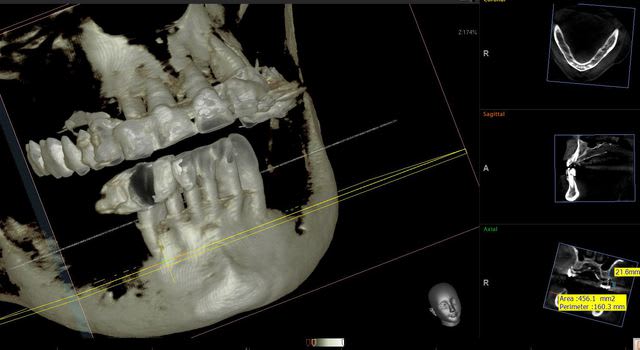

j' ai des coupes de chez morita

dés que je peux j'en mets de vatech

Capture morita 2 stjceh - Eugenol

Capture morita x66gah - Eugenol

Coupes morita fffknv - Eugenol